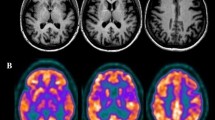

Results and interim discussion. The lesion mainly involved posterior LH regions (Fig. 5a, Supplementary Table S1), namely the occipital pole, the lingual gyrus, the intracalcarine cortex, the lateral occipital gyrus, the fusiform and parahippocampal gyri, the posterior cingulum and the precuneus. The lesion also involved middle-inferior splenial fibers (Fig. 5b). The disconnectome analysis (Fig. 5c, Supplementary Tables S2 and S3) demonstrated the disconnection from the lesion site of the splenial fibers, together with a set of white matter tracts: the cingulum, the inferior fronto-occipital fasciculus, the optic radiations, the fornix, the long and posterior segments of the arcuate fasciculus, the superior and inferior longitudinal fasciculi.

(a) 3D rendering of the lesion after normalization to the standard MNI template; (b) 2D plot of the lesion at the level of the medial sagittal plane. Fluctuations in voxel intensity at the boundary of the lesion map are a byproduct of spatial normalization; (c) 3D rendering of the disconnectome map based on the patient’s lesion and structural connectivity estimates based on 100 healthy controls. For the original MRI scan see Bonandrini et al. (2020) (colors online and in PDF)

As far as the lesion is concerned, the anatomical analysis demonstrated that in AA it encompassed the most posterior (and medial) LH cortical regions, involving the occipital pole, the lingual gyrus, the intracalcarine cortex, the lateral occipital gyrus, the fusiform and parahippocampal gyri, the posterior cingulum and the precuneus. In line with a previous analysis on a more limited reference sample of healthy controls (Bonandrini et al. 2020), we conducted a lesion-based structural disconnectome analysis, which allows to estimate, based on structural connectivity in healthy controls, the probability - from 0 to 1 - of each volume unit in the brain (voxel) of being disconnected from the lesion site (Thiebaut de Schotten et al. 2015). The present disconnectome analysis brings evidence for the critical disconnection of the lesion site (largely involving left ventral occipito-temporal areas) from the RH occipital lobe and to LH language areas. Furthermore, voxels in the middle-inferior callosal splenial fibers, together with a set of white-matter tracts (bilaterally, but mostly in the LH), as the cingulum, the inferior fronto-occipital fasciculus, the optic radiations, the fornix, the long and posterior segments of the arcuate fasciculus turned out to be disconnected from the lesion site (Fig. 5, Supplementary Table S2 and S3). This provides an anatomical account for the visual-verbal disconnection that defines OA: the lesion interrupts the flow of visual information from the RH to the LH occipital cortices, as well as that from LH visual cortices to LH language areas.

In OA, because of right homonymous hemianopia, visual information is processed by the RH, but it cannot be adequately transferred to the LH for lexical activation, due to the splenial disconnection (Schnider et al. 1994; see Supplementary Figure S1). The disconnectome analysis performed in AA suggests an extensive damage to the splenium, and that the flow of semantic information is most likely to stream leftward through the spared anterior commissure (Fig. 5, see also Fig. 2 for graphical representation of AA’s lesion and disconnection profile with reference to the neurocognitive model). The anterior commissure mediates the connection among inter-hemispheric temporopolar regions (Catani and Thiebaut de Schotten 2008; Mesulam 2023). The inter-hemispheric transfer of information would thus happen more likely after semantic access in RH. It is in the LH that semantic information would trigger activation of the corresponding lexical label. We speculate that in OA the callosal damage would cause impaired or lower, less specific semantic activation among competitors, and consequently naming deficits. Indeed, errors are predominantly semantic, as semantic paraphasias and semantic perseverations. A qualitative analysis of naming errors revealed that AA committed frequent vertical semantic perseverations, namely naming responses biased by those given to previous stimuli (Lhermitte and Beauvois 1973), in line with what described in other cases affected by OA, as well as with the results obtained by Plaut and Shallice (1993) in a simulation study. Differently from lexical perseverations of typical aphasia (Hepner and Nozari 2020), the type of perseveration errors frequently found in OA are considered “a peculiar mingling of semantic errors, perseverations, and descriptions of morphological features of the object” (Beauvois 1982). Explanations in terms of lack of inhibitory processes (Lhermitte and Beauvois 1973), inhibitory connections (Goldenberg and Karlbauer 1998), and damage to “clear-up units” (Plaut and Shallice 1993) have been suggested. To explain typical aphasia perseverations at various levels (e.g., whole words, isolated semantic features, phonemes), Cohen and Dehane (1998) proposed the residual activation model, according to which deafferentation causes persistent activation of information that results in perseverations.